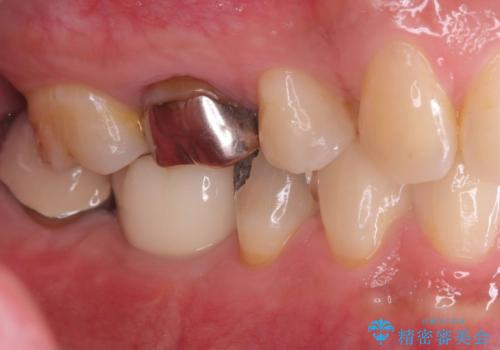

銀歯を除去後、やはり銀歯の下は虫歯になっていましたので、虫歯を除去した後にオールセラミッククラウンで被せました。

MOD窩洞のインレーは破折強度が弱くたびたび今回の症例のように歯が欠けてしまうケースがあります。破折ラインが歯根までいっていると抜歯となってしまう場合もあります。

破折から歯を守る為にはインレーよりもクラウンの方が優れています。